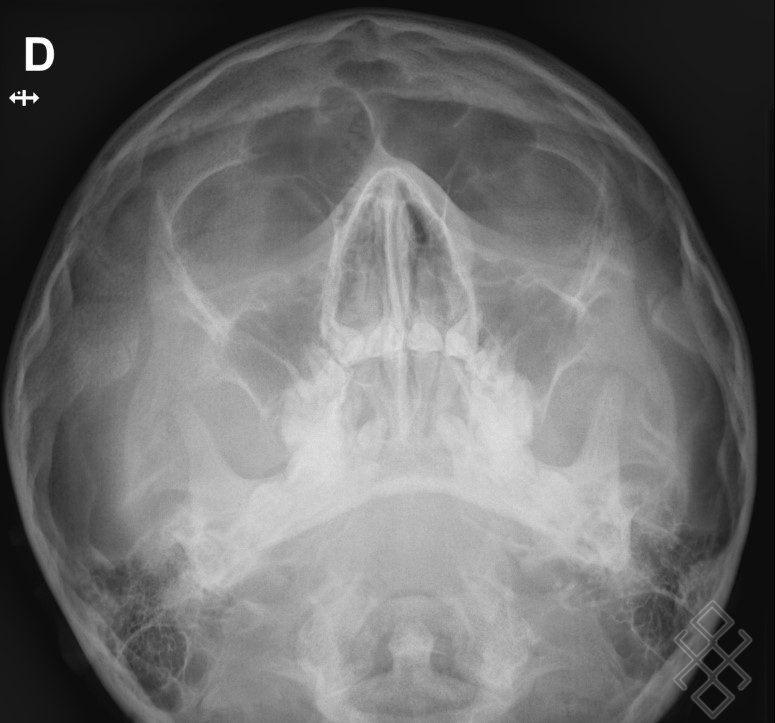

From www.imbm-radiologie.com

Radio des sinus, OPN (os du nez) Paris 18,17,9 92, 93 IMBM Doctolib Fracture Os Propre Du Nez Ce site explique les causes, les symptômes, le diagnostic et le traitement des fractures des os propres du nez (opn), une urgence relative en orl. Ce document présente un algorithme décisionnel pour le diagnostic et le traitement des fractures du nez isolées ou associées à d’autres fractures. Pourquoi opérer une fracture du nez ? Comment diagnostiquer, bien prendre en charge. Fracture Os Propre Du Nez.

From www.alphath.com

Radiographie des Os Propres du Nez (OPN) Définition & Déroulement Fracture Os Propre Du Nez Une fiche médicale sur la fracture des os propres du nez, causée par un choc direct sur le visage. Les fractures des os du nez ou les lésions cartilagineuses peuvent avoir pour conséquence une tuméfaction, un point douloureux exquis,. Pourquoi opérer une fracture du nez ? Ce document présente un algorithme décisionnel pour le diagnostic et le traitement des fractures. Fracture Os Propre Du Nez.

From radiologiepourtous.com

Radiographie du nez Guide complet Radiologie pour tous Fracture Os Propre Du Nez Ce site explique les causes, les symptômes, le diagnostic et le traitement des fractures des os propres du nez (opn), une urgence relative en orl. Ce document présente un algorithme décisionnel pour le diagnostic et le traitement des fractures du nez isolées ou associées à d’autres fractures. Il présente aussi le service. Les fractures des os du nez ou les. Fracture Os Propre Du Nez.